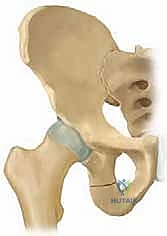

جراحة قطع عظم الحوض الثلاثي (TIO) هي إجراء جراحي يعيد توجيه التجويف الحقي لتحسين تغطية رأس الفخذ وعلاج خلل تنسج الورك، خاصة في الأطفال والمراهقين. يتم من خلال قطع عظام الحوض الثلاثة (الحرقفة، الإسك، العانة) لتمكين دوران التجويف الحقي حول رأس الفخذ، مما يزيد من استقراره ويقلل من خطر التهاب المفاصل المبكر.

من خلال إجراء قطوع دقيقة في عظام الحوض الثلاثة (الحرقفة، الإسك، العانة)، يتم تحرير التجويف الحقي بالكامل ليتم تدويره حول رأس الفخذ، مما يضمن استقراراً ميكانيكياً حيوياً للمفصل، ويمنع الخلع المتكرر، ويقي المريض من خطر الإصابة بالفصال العظمي (التهاب المفاصل التنكسي) المبكر الذي قد يستدعي زراعة مفصل صناعي في سن مبكرة.

لفهم أهمية جراحة (TIO)، يجب أولاً فهم التشريح المعقد لمفصل الورك. يُصنف مفصل الورك على أنه مفصل كروي حقي (Ball-and-Socket Joint). تتكون "الكرة" من رأس عظم الفخذ (Femoral Head)، بينما يتكون "التجويف" من الحق (Acetabulum) وهو جزء من عظم الحوض.

في حالات خلل التنسج، يكون التجويف الحقي ضحلاً جداً (غير عميق بما يكفي) أو مائلاً بزاوية غير طبيعية. هذا يعني أن "الكوب" لا يغطي "الكرة" بشكل كافٍ. نتيجة لذلك:

بمجرد اكتمال هذه القطوع الثلاثة، يصبح التجويف الحقي (الكوب) منفصلاً تماماً عن بقية الحوض، مع بقاء إمداداته الدموية سليمة.

4. إعادة التوجيه والتدوير (Rotation & Redirection)

باستخدام أدوات خاصة، يقوم الدكتور هطيف بتدوير التجويف الحقي الحر في ثلاثة أبعاد (للأمام، وللخارج، وللأسفل) حتى يغطي رأس عظم الفخذ بشكل مثالي وميكانيكي سليم. يتم التحقق من الزاوية الجديدة فوراً داخل غرفة العمليات باستخدام جهاز الأشعة السينية المتحرك (C-arm).